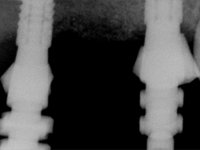

Diagnostic wax-up to allow the development of an ‘radiological template’ to proceed with a CT scan, in order to do an implant planning guided by the planned prosthesis.

The wax-up allowed us to do a mock-up that worked also as a radiological template. The CT-scan was imported to an implant planning software where three dental implants were simulated, and a surgical guide developed.